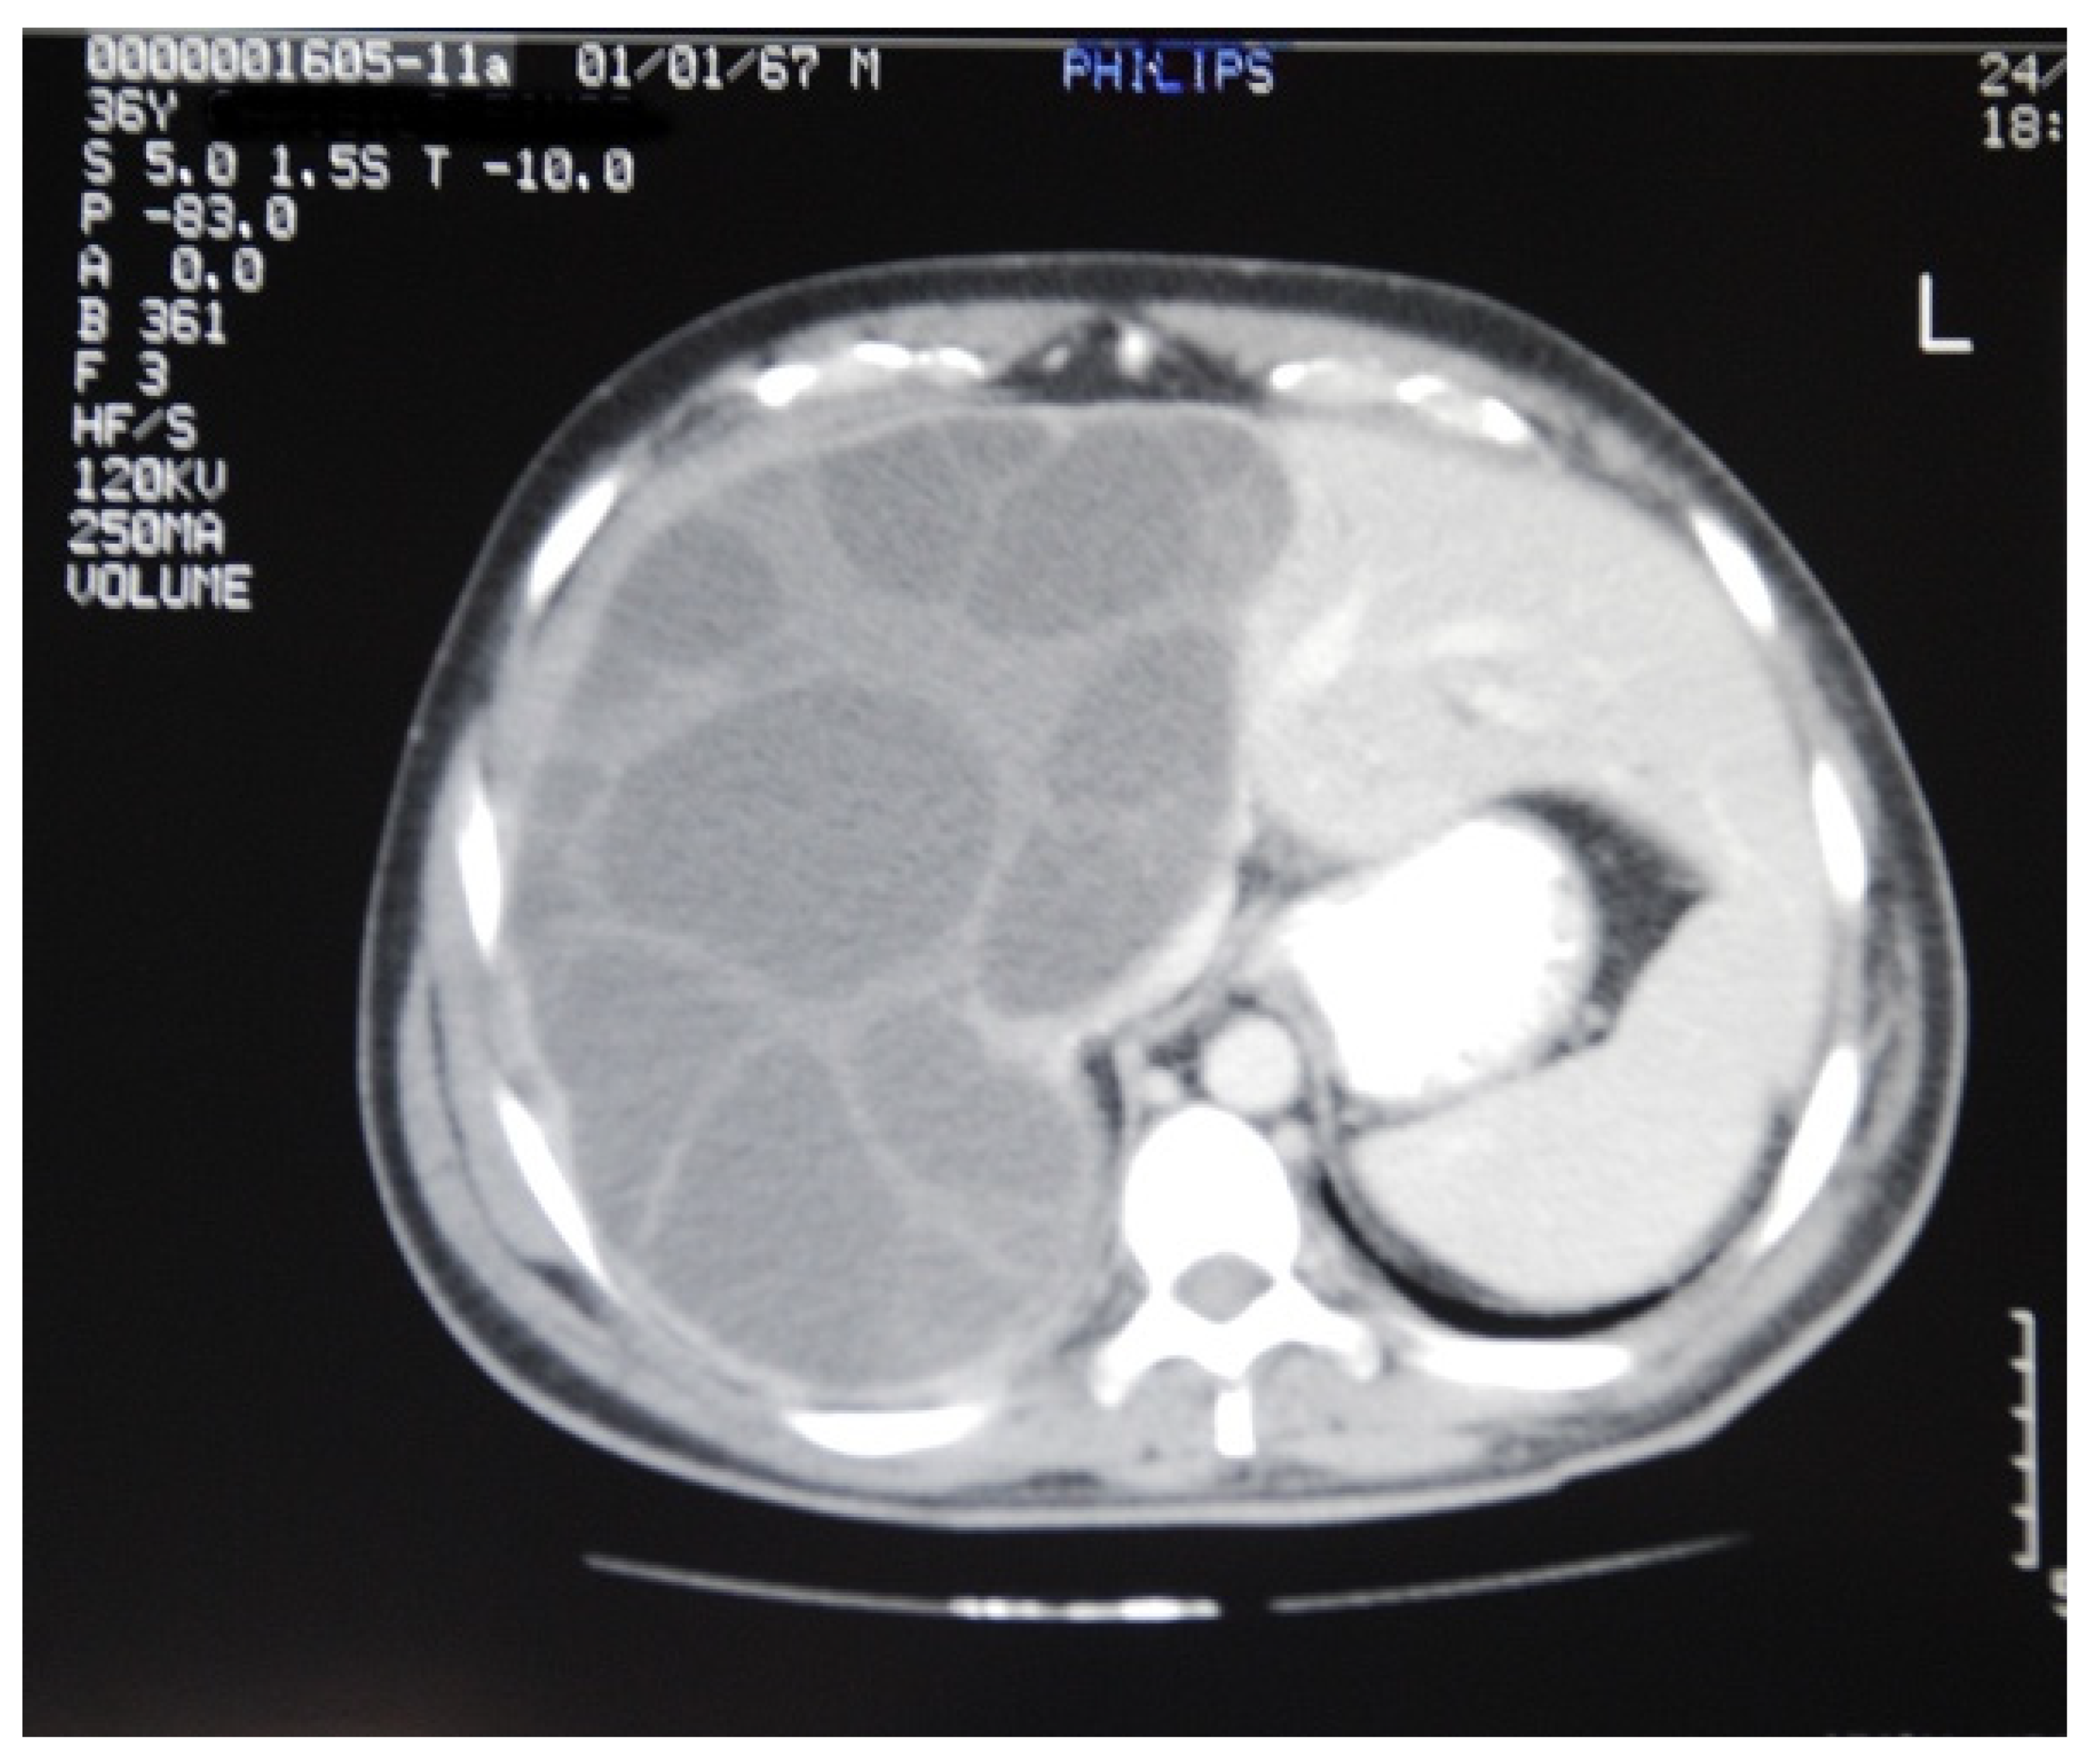

| Computer Tomography | 2/6 (33%) | 1/6 (17%) | 2/2 (100%) | 2/2 (100%) | 1/2 (50%) | 8/18 (44%) |